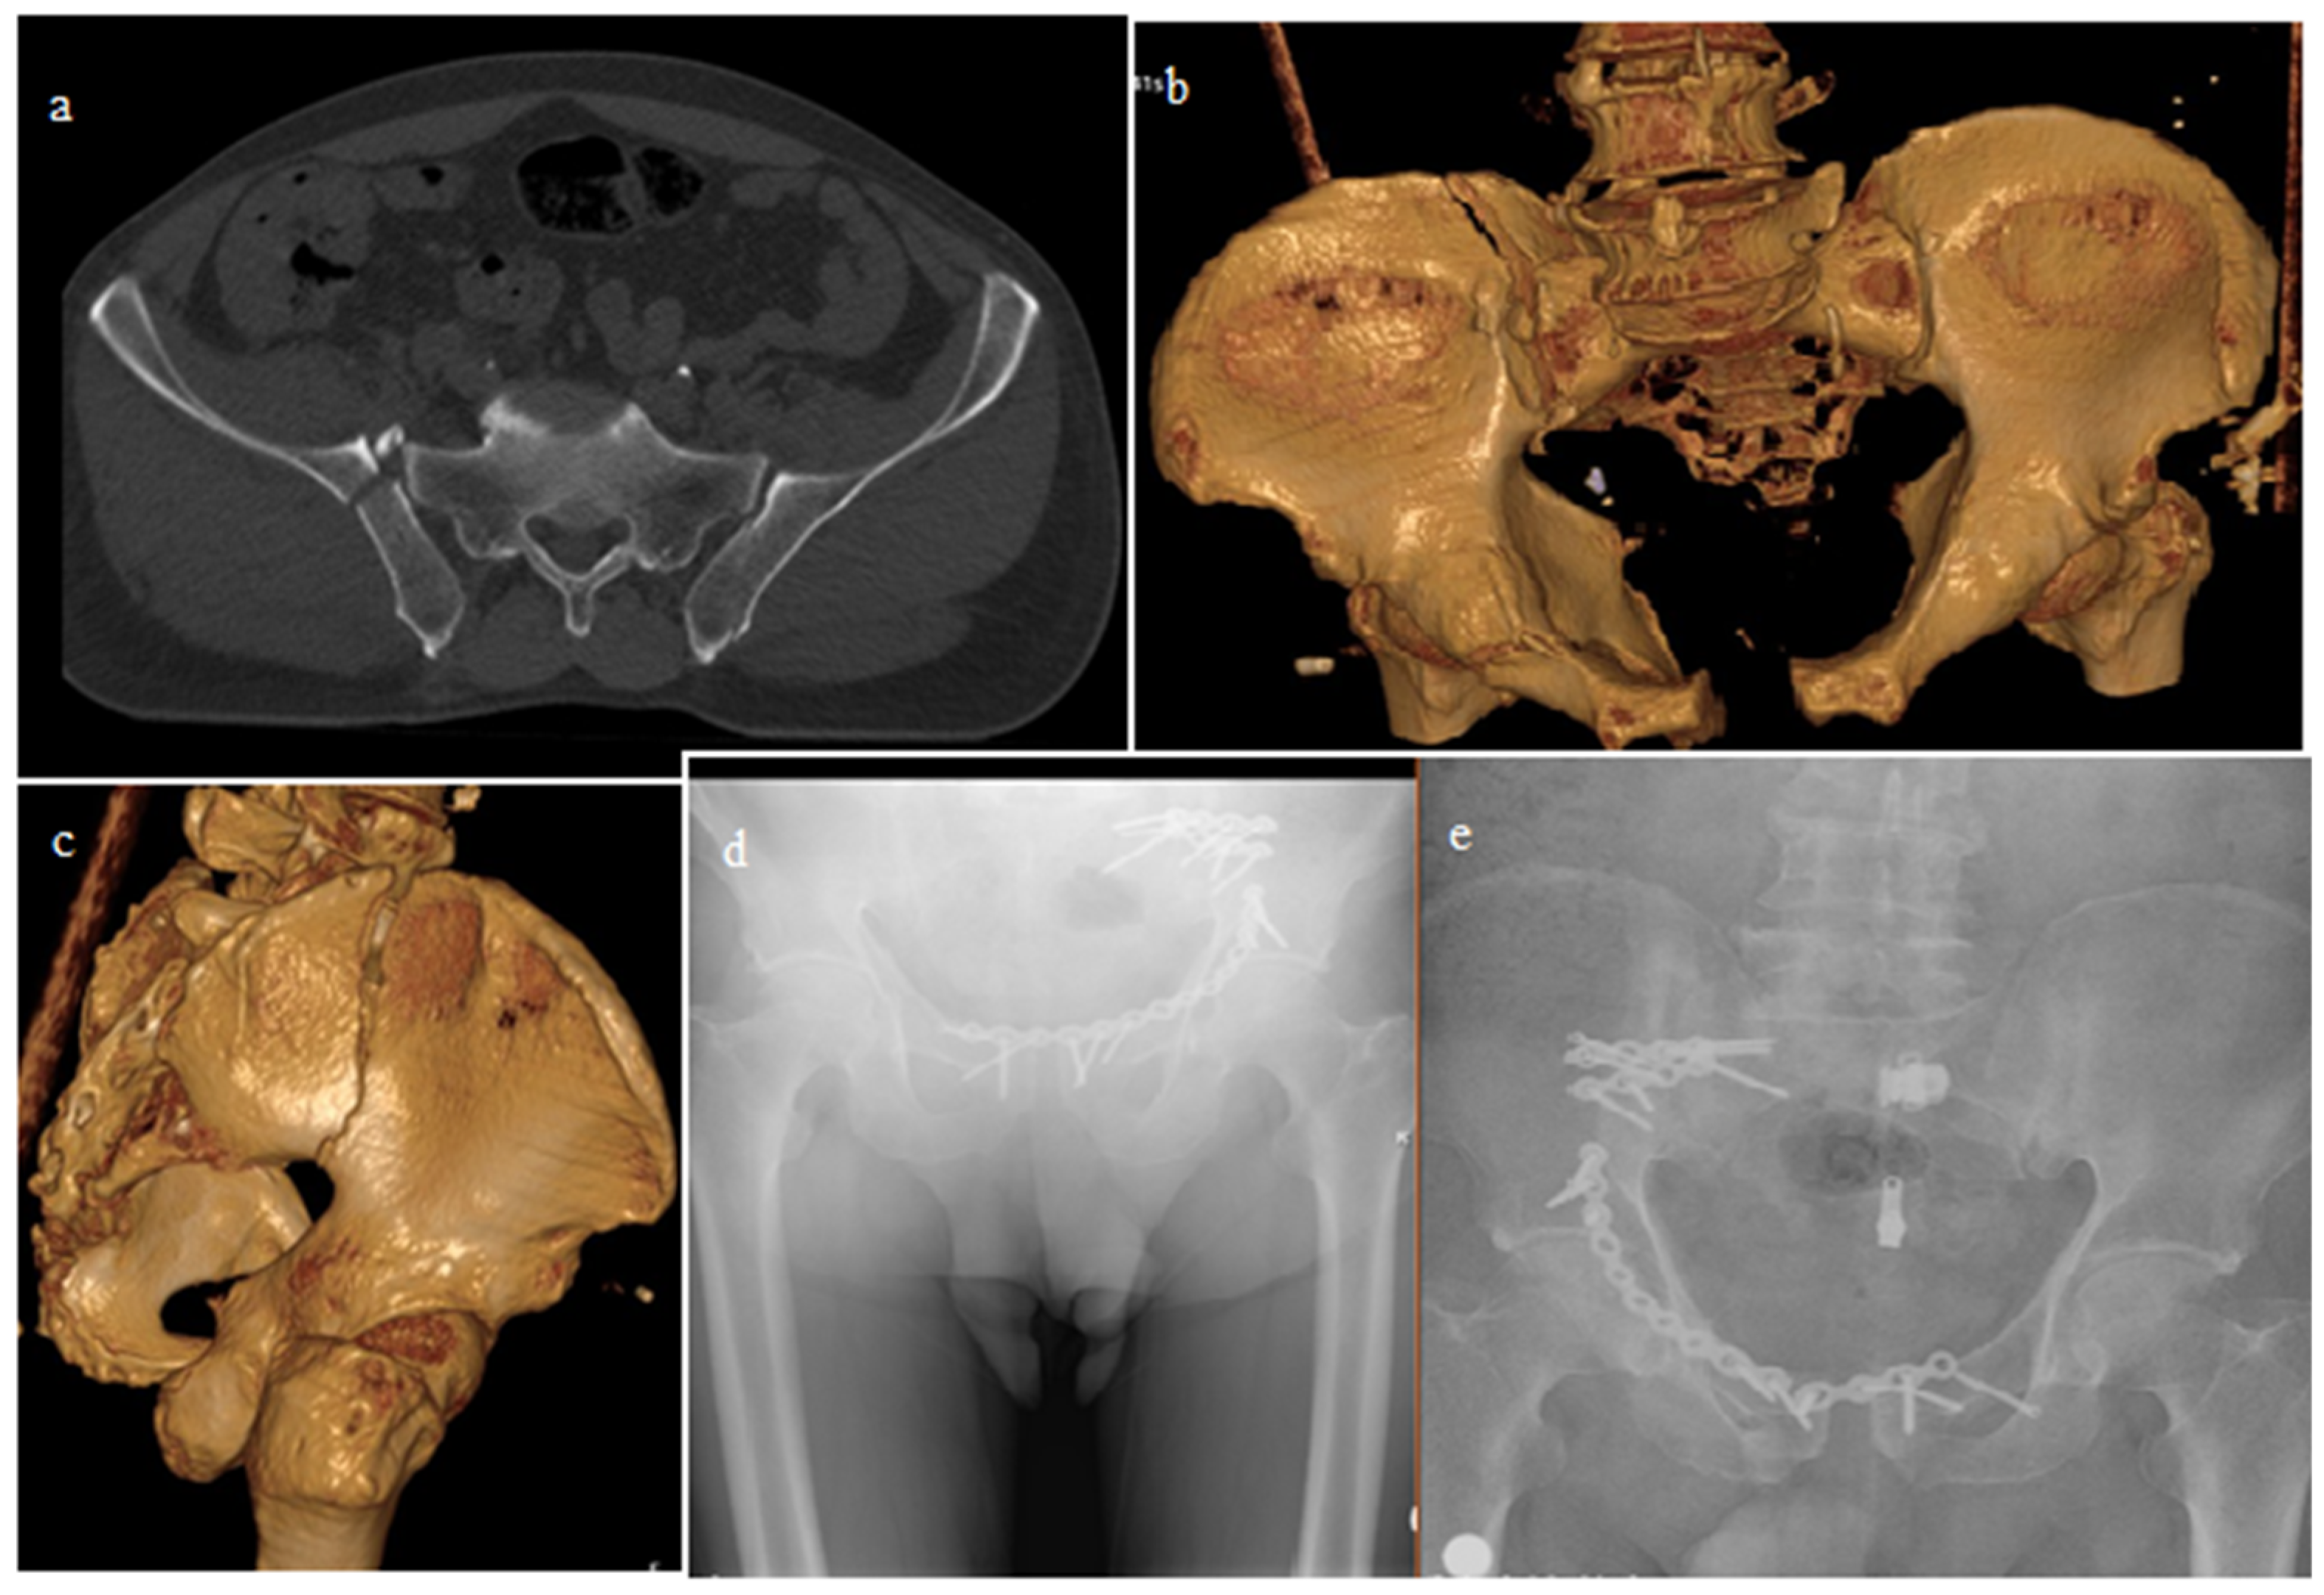

| Closed reduction + ISS | 59 | 48.7 |

| Open reduction + Anterior PS | 36 | 29.75 |

| Open reduction + Posterior PS | 15 | 12.4 |

| Open reduction + ISS | 11 | 9.1 |